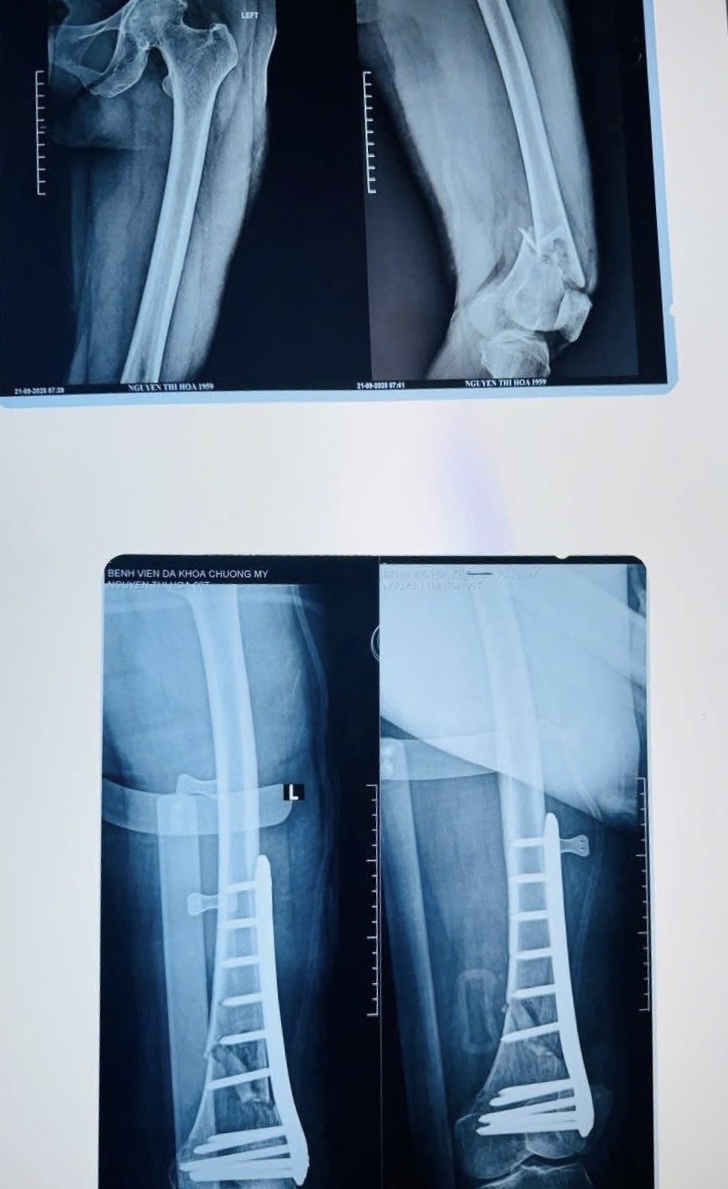

Ngày 21/9/2025 Khoa Ngoại - Bệnh viện đa khoa Chương Mỹ đã tiếp nhận bệnh nhân Nguyễn Thị H, 66 tuổi, thường trú tại Đông Sơn, Phú Nghĩa vào viện trong tình trạng đau, mất vận động đùi trái sau tai nạn giao thông.

Tại BVĐK Chương Mỹ, kết quả X-quang cho thấy bệnh nhân bị gãy hở 1/3 dưới xương đùi trái, một chấn thương phức tạp kèm nguy cơ mất máu và choáng chấn thương. Trước tình huống khẩn cấp, ê-kíp bác sĩ Khoa Ngoại tổng hợp đã nhanh chóng hội chẩn và quyết định phẫu thuật cấp cứu kết hợp xương bằng nẹp vis.

Đây là một ca mổ khó do gãy hở, tổn thương cơ và mạch máu lớn. Với tinh thần khẩn trương, chính xác, kíp phẫu thuật đã xử trí thành công cho người bệnh. Sau phẫu thuật, bệnh nhân được truyền máu, truyền dịch, dùng kháng sinh dự phòng và hiện sức khỏe đã ổn định, đang tập phục hồi chức năng tại khoa.